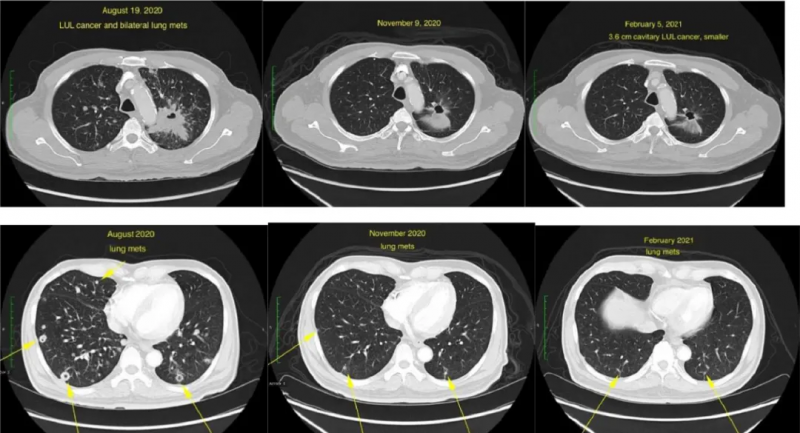

1、IV期肺癌

晚期肺癌SOSTM1-NTRK1融合,接受拉罗替尼治疗6周后,不仅最大的那个病灶明显缩小(6×5cm至4.6×4.2cm),全身的肿瘤数量也出现了骤减(肺部病灶由之前扫描的100个减少到25个),75个病灶消失!

肺及纵隔病灶:治疗前治疗6周治疗20周